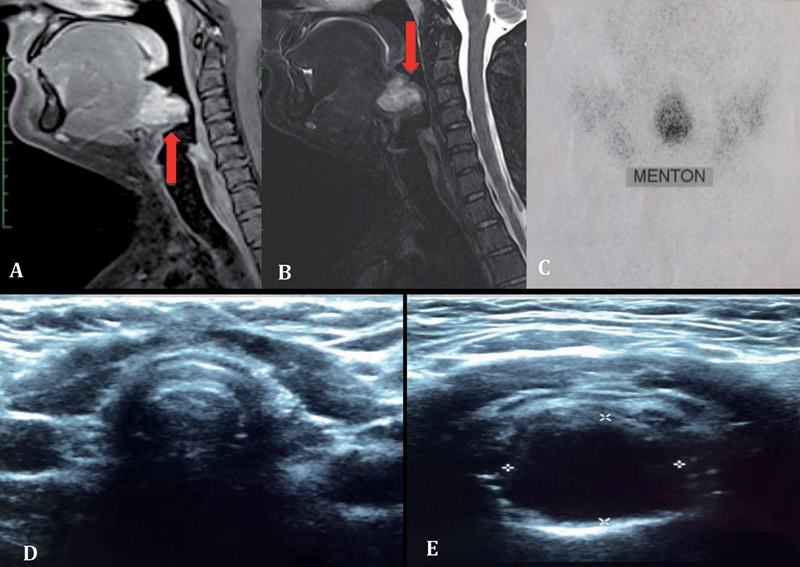

Mujer de 23 años, fumadora de 2 paquetes/año, con antecedentes de hipotiroidismo desde los 20 años en tratamiento con levotiroxina, subtratada. Consulta por cuadro de 5 meses de evolución caracterizado por odinofagia leve y sensación de cuerpo extraño orofaríngeo, asociado a episodios de sangrado bucal de mal olor. Se realiza nasofibroscopía encontrando en línea media una masa redondeada en la base de la lengua cuya biopsia describe neoplasia tiroidea con patrón sólido y ulcerada que infiltra la cápsula tumoral sin traspasarla (Figura 1A y 1B) constituida por células epiteloideas de gran tamaño formando nidos, cordones, trabéculas y áreas sólidas con núcleos irregulares atípicos (Figura 1C). La Inmunohistoquímica demostró: Factor 1 de Transcripción Tiroidea (TTF-1) (+), Ciclina D1 (+), Citoqueratina 7 de membrana en células tumorales (+), HBME -1 (+), Focal de algunas células tumorales, Citoqueratina 20 (-), CEA(-) y Sinaptofisina (-) (Figura 1D) RM cervical muestra ocupación de la vallécula por tejido de partes blandas, de estructura discretamente heterogénea de baja señal en T1 e hiperintenso en T2 que se impregna tras la administración de gadolinio, de 20 x 20 x 22 mm en los ejes mayores y que desplaza la epiglotis hacia caudal. No se visualiza glándula tiroides en el opérculo toráxico ni región cervical anterior (Figura 2A y B). En cintigrama tiroideo se observa concentración del radiofármaco sólo en un área ovalada de localización sublingual en la línea media (Figura 2 C) concluyendo presencia de TTE. Ecografía cervical confirma lecho tiroideo vacío (Figura 2D) y un nódulo sólido hipoecogénico de 19 x 20 x 20 mm en base de la lengua (Figura 2E) sin evidencia de extensión locorregional. Se presenta en Comité de Tiroides, indicándose cirugía. En el procedimiento se ve y palpa tumor en base de lengua de aproximadamente 40 mm de diámetro mayor, friable, bastante superficial, bien delimitado. Se secciona la lengua en línea media, se identifica tumor resecándolo completamente. La biopsia definitiva concluye carcinoma folicular mínimamente invasor con dos permeaciones vasculares. Se indica radioablación con 100 mCi de I-131, el rastreo sistémico a los 7 días fue negativo. Los valores de TSH y Tg se presentan en Tabla 1. Actualmente la paciente está en seguimiento bajo terapia de sustitución con levotiroxina, eutiroidea desde el punto de vista clínico y de laboratorio.